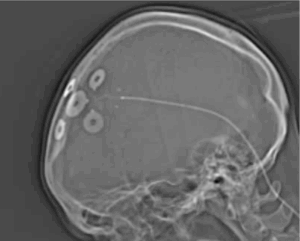

A new therapy for certain types of seizures is known as EASEE®, which stands for Epicranial Application of Stimulation Electrodes for Epilepsy. This delivers electricity to the part of the brain believed to be causing seizures. This is believed to stabilise the brain’s activity and reduce seizures. A major advantage of this procedure is that there is no surgery on the brain, and the effect won’t fluctuate like it can with medications.

In terms of benefit, there is one main study that suggests seizures can be reduced by half in about 2 out of every 3 people at 2 years. The results are likely to be best if we know the seizures are coming from a clear area of the brain.

Practically, this involves an operation to place a 5cm pad under the scalp and attached it to the skull, which is then connected to a battery sitting under the collar bone. This is completed as a small operation under general anaesthetic as a day-case procedure. A major advantage to this is there is no brain surgery – everything is placed on the skull and the chance of any complication is very low.